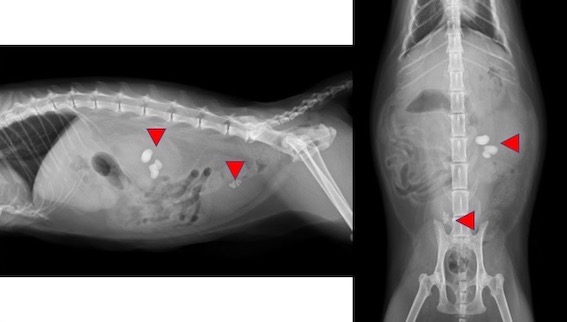

今回の症例は、左側の腎盂内に複数個の結石があり、その1つが近位尿管に閉塞していました。同時に膀胱結石も認められました。

レントゲン検査画像です。